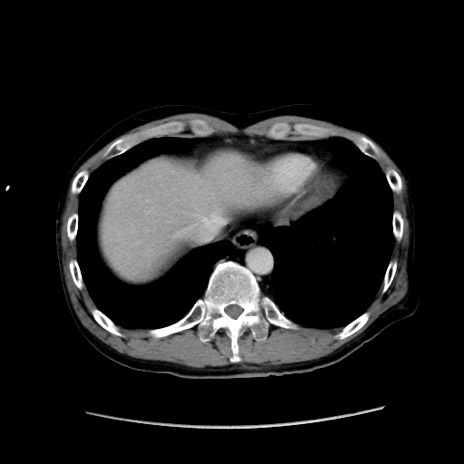

冠状断像